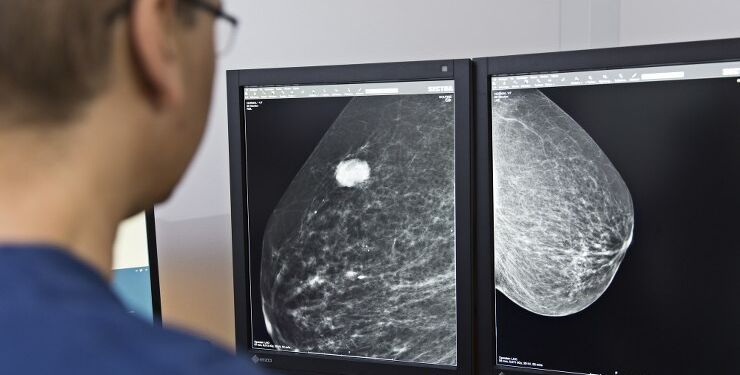

Regionen har formået over en længere periode at være den bedste af alle fem regioner til at operere brystkræftpatienter til tiden. De nye tal cementerer den position, og det er jeg rigtig glad for på vegne af brystkræftramte kvinder i Nordjylland, roser Orla Kastrup Kristensen.

Regionsformanden reagerer på Sundhedsdatastyrelsen nye tal, der netop er udkommet. Tallene viser, hvordan det er gået for landets regioner med at overholde de såkaldte forløbstider for udredningen af kræftpatienter i 3. kvartal af i år.

Her blev 99 pct. af alle brystkræftforløb, der endte med kirurgisk behandling, gennemført til tiden i Region Nordjylland. Det er et bedre resultat end i de øvrige regioner. Gennemsnittet for samtlige regioner er 52 pct.

Især Region Sjælland og Region Hovedstaden trækker gennemsnittet ned. I de to regioner lykkedes det i 3. kvartal kun at gennemføre forløbstiderne i henholdsvis 32 og 25 pct. af tilfældene.